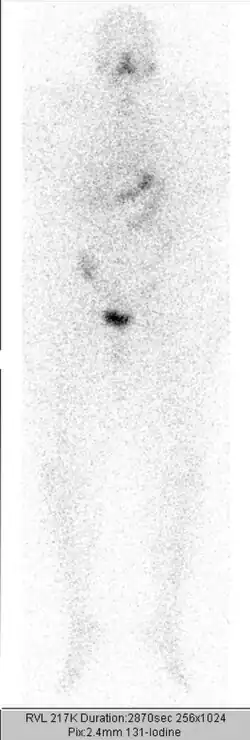

Einige Tage nach der Therapie wird ein Ganzkörperszintigramm angefertigt. Die Therapie wird in etwa dreimonatigen Abständen wiederholt, bis weder das Szintigramm, das Ultraschallbild der Halsregion, noch der Tumormarker Thyreoglobulin einen Hinweis auf nennenswertes verbliebenes Schilddrüsengewebe (gutartig oder bösartig) geben. Eine Gesamt-Aktivität über alle durchgeführten Radiojodbehandlungen von bis zu 74 GBq (2000 mCi) wird bei sonst gesunden Patienten meist problemlos vertragen. Bei höherliegenden Aktivitäten ist mit einem erhöhten Risiko für eine dauerhafte Schädigung des Knochenmarks als blutbildendes Organ zu rechnen.

Der Ablauf – mit Jodkarenz, Stimulation des TSH mit anschließender Bestimmung des Tumormarkers Thyreoglobulin und oraler Gabe des Jods sowie der Durchführung der Ganzkörperszintigrafie – entspricht dem Ablauf bei der ablativen Therapie. Unterschiedlich ist dagegen die Höhe der verabreichten Aktivität, üblich sind etwa 100 bis 400 MBq Jod-131 oder 40 bis 200 MBq Jod-123.